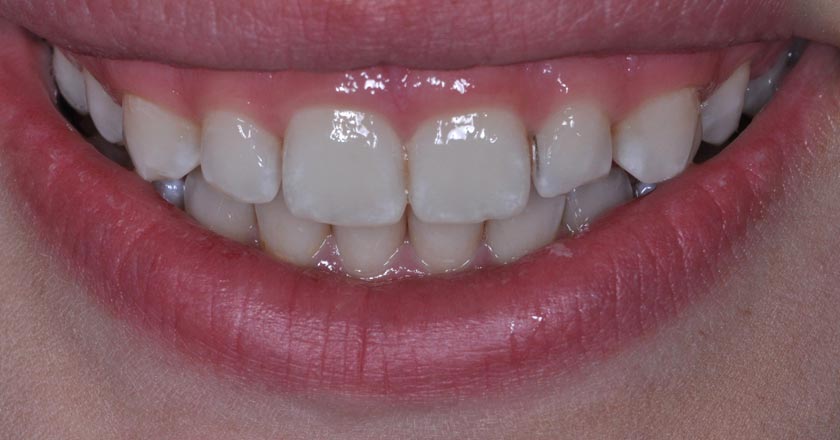

Gummy Smile - Before And After

Gummy smile correction – before treatment 1

Gummy smile correction – after treatment 1